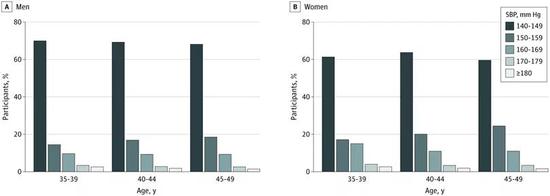

这项对中国冠心病医疗结果评价和临床转化研究(China PEACE)中,近90万35-49岁中青年人开展的横断面研究显示,有23.5万中青年人患有高血压,整体的患病率达到26.2%,高血压患者占比超过四分之一。

从整体来看,6.28万ISH患者约占全部90万参与者的7%,患者平均年龄为45岁,呈现女性多于男性(33.2% vs。 19.4%),东部地区多于西部等特点,与普通人相比,ISH患者有肥胖、糖尿病、抽烟饮酒等心血管危险因素的比例更高。

参与者的年龄分布和血压状况

参与者的年龄分布和血压状况有超过15%的ISH患者收缩压已经在160mmHg以上,但在全部的ISH患者中,只有13.3%接受了相应治疗。没有接受过治疗的患者中,则只有6.8%意识到自己患有高血压。